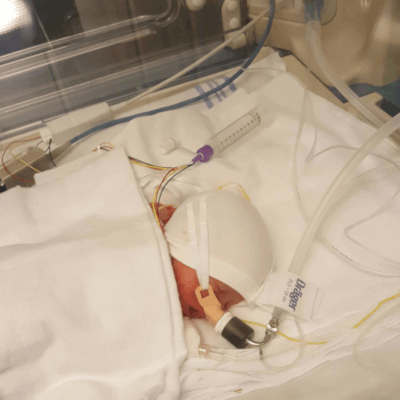

Kort efter kl 02.00 kommer baby A til verden. Vi høre et svagt skrig og straks er jordemoderen ude af døren med hende. Både baby B og C kommer ud kl. 02.01. De skriger også – svagt, men de skriger. De lever!

Martin følger med den sidste baby ud i børneundersøgelsesrummet. de har taget mine børn og er gået med. Det jeg frygtede allermest lige fra starten, var lige sket. De havde taget mine børn.

Kl. 03.10 sendte Martin billeder af pigerne – De havde det godt. En time senere blev jeg kørt op til dem.